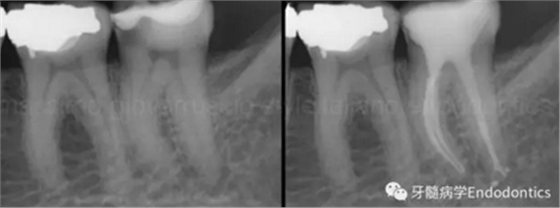

圖9.當(dāng)遇到了根尖方向的阻力,退出銼,使用銼預(yù)彎鉗(Endobender)平滑的預(yù)彎銼尖部的2mm,將銼上的硅膠止動(dòng)片的方向指示調(diào)成朝向銼彎曲的方向,這樣你就可以繞過(guò)障礙形成通路了。

圖11.術(shù)后X片顯示完成了根管的三維充填并很好地保留了復(fù)雜的解剖形態(tài)結(jié)構(gòu)。

圖14.一旦通過(guò)了障礙,應(yīng)避免將銼退出至障礙水平,因?yàn)殇S會(huì)不可避免的被拉直,之后除非將銼完全退出,重新預(yù)彎,重新插入,否則無(wú)法通過(guò)障礙。在S形彎曲根管內(nèi),存在兩處障礙,當(dāng)銼繞過(guò)根管內(nèi)第一處障礙后會(huì)在第二個(gè)彎處再次遇到根尖方向的阻力。在這樣的病例中,將銼稍微回退少許,旋轉(zhuǎn)180度,輕輕扭動(dòng),觀察銼是否能到達(dá)全長(zhǎng)。